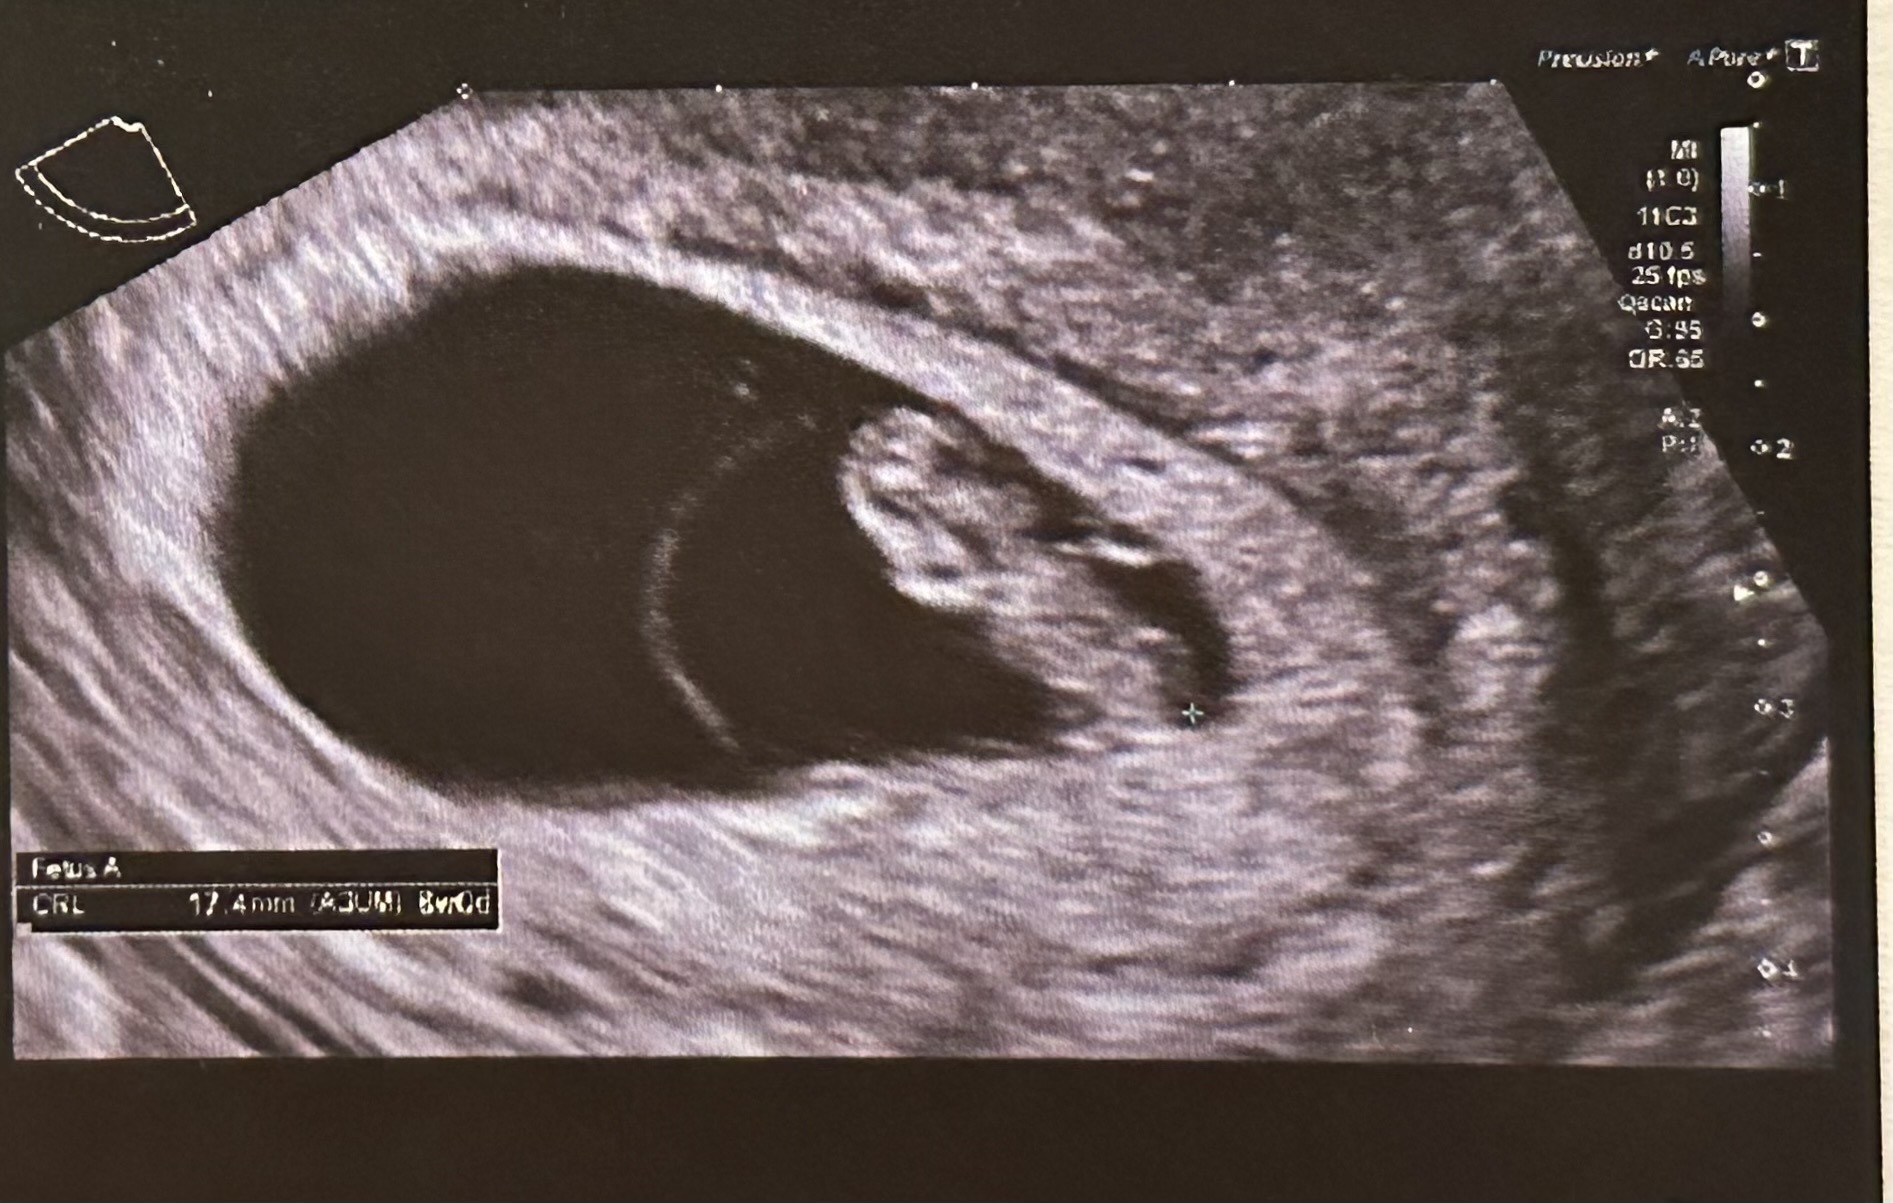

오늘이 8주 4일인데 계속 무증상이었는데 초음파도 자주 못 하는 상황이라 너무 걱정되더라구요. 딱히 달라진게 없으니 실감도 안나고 제 눈으로 보기 전까진 안심이 안됐어요 ㅠㅠ 불안하면 아기도 느낀다 해서 최대한 맘 편히 가지려고 해도 제가 무뎌서 그런 건지 임신 전이랑 별반 다른게 없는 느낌 ㅜㅜ 가슴이 딱딱해진 거 같다가듀 말랑해지고 속이 메슥거리는 거 같다가도 잘 먹히고. 화장실도 자주 들락날락 거리는 거 같다가도 잘 자다 보니 애기가 잘 있는건지 매일 걱정했어요 ㅠㅠ 8주 2일차에 드디어 초음파를 보고 왔어요!! 키는 1.74에 심박수도 173으로 건강하게 잘 커주고 있더라구요 ㅠㅠ 너무 기특하고 감사했어요. 무증상 동기들 너무 걱정마세요 ❤️❤️❤️아가들이 우리 생각보다 강하대요 🥰 그나자나 울 애기 딸일까요 아들일까요 🤔ㅎㅎㅎㅎ